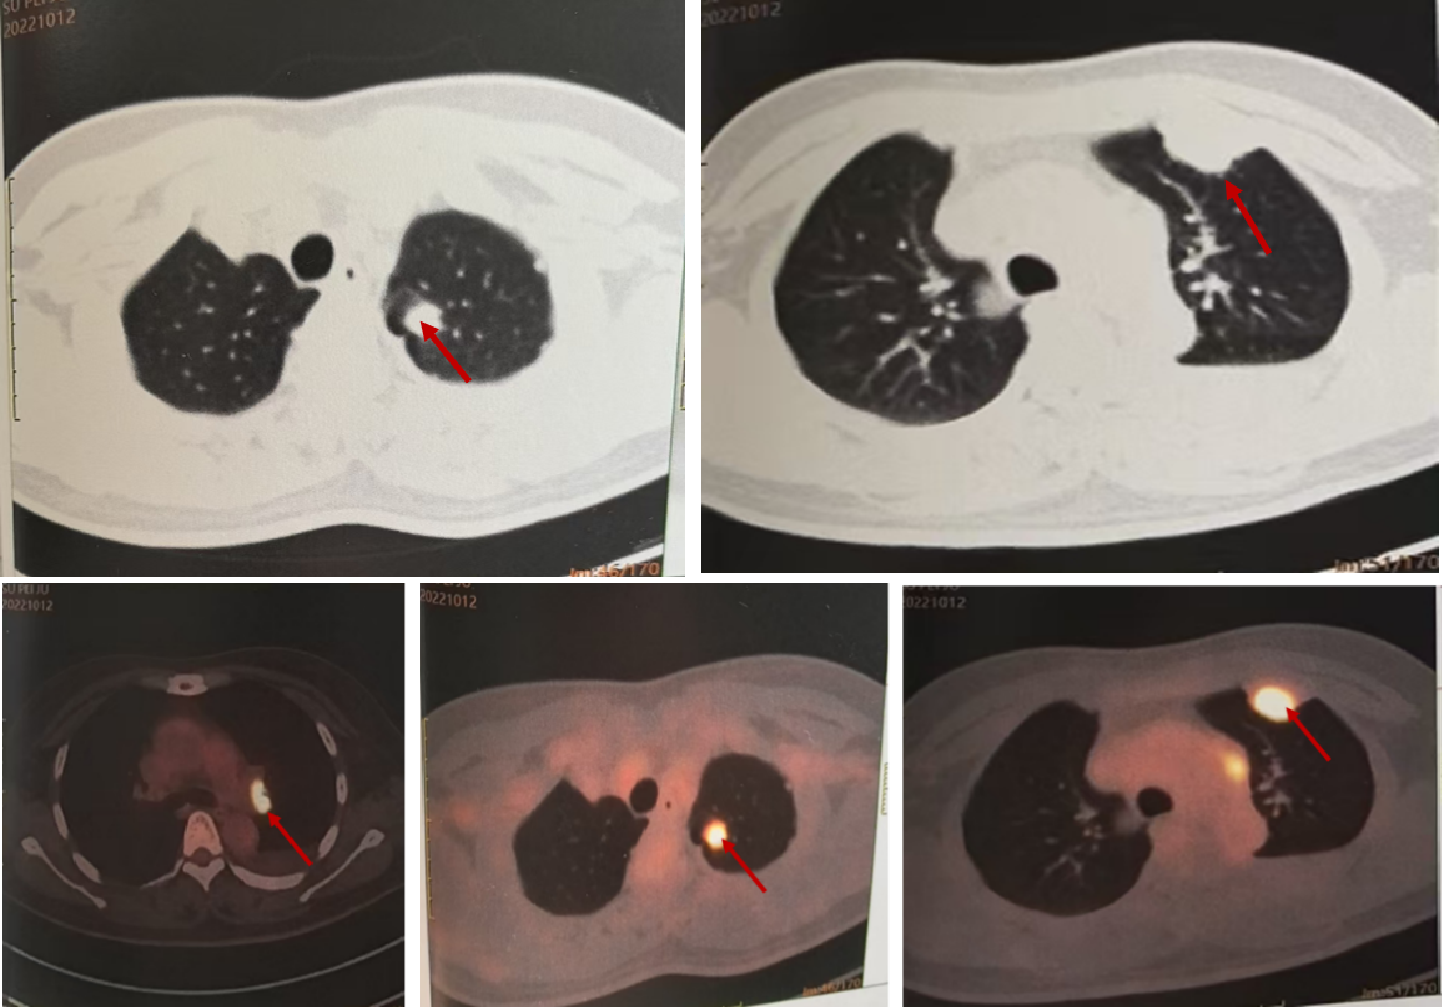

2022-10-12 PET-CT(图1):1.左肺上叶FDG高代谢结节;左肺胸膜多处FDG高代谢灶;双侧锁骨区多发FDG略高代谢小淋巴结、簇状分布;左肺门、纵隔、膈肌脚间隙、上腹部、腹膜后多发FDG高代谢淋巴结;右侧第5前肋、胸骨体、左侧坐骨,肝脏多发FDG高代谢灶,符合肺恶性肿瘤并多发转移。2.左侧胸腔积液。3.右肺上叶磨玻璃结节,未见FDG代谢,肿瘤不除外。